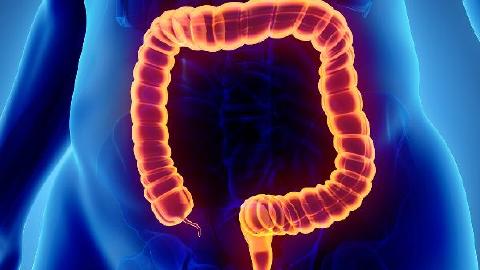

鈣與高血壓的關(guān)系主要體現(xiàn)在鈣離子參與血管平滑肌收縮調(diào)節(jié)、影響腎素-血管緊張素系統(tǒng)活性等方面,適度補(bǔ)鈣可能有助于部分高血壓患者控制血壓。

鈣離子是血管平滑肌收縮的關(guān)鍵介質(zhì),細(xì)胞內(nèi)鈣濃度升高會(huì)導(dǎo)致血管收縮。鈣通道阻滯劑類降壓藥通過(guò)阻斷鈣內(nèi)流發(fā)揮降壓作用。